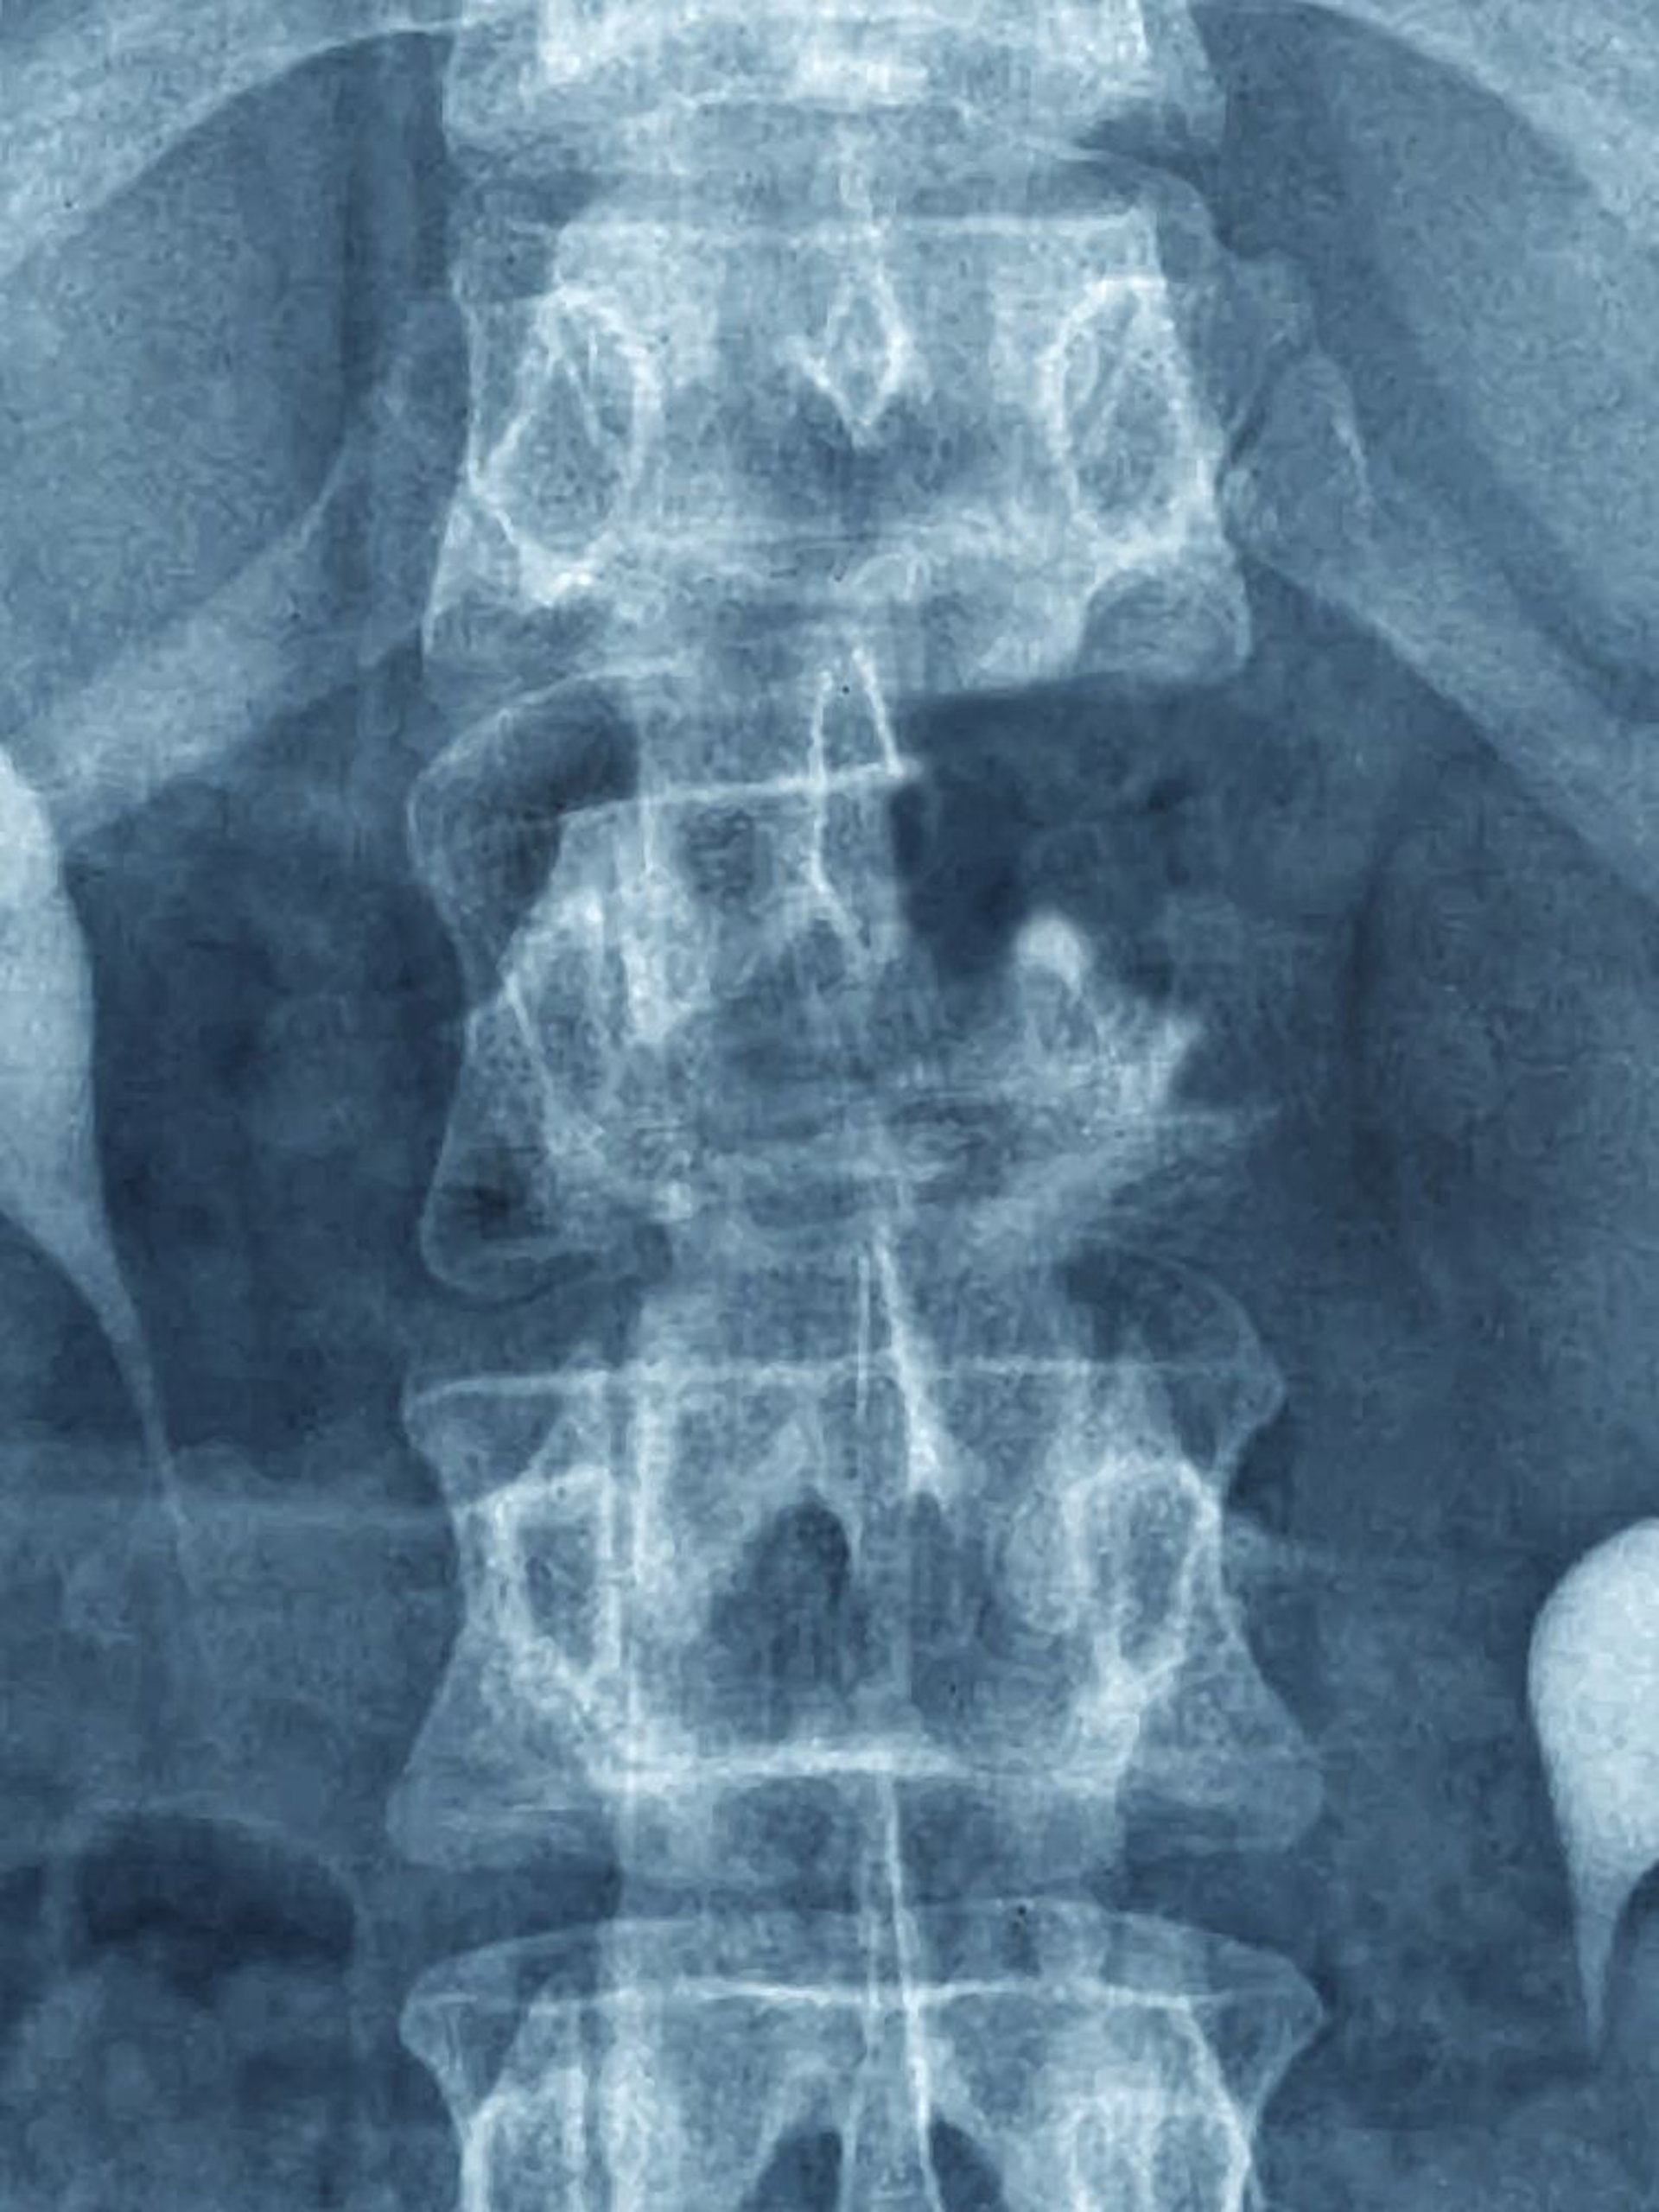

Cáncer óseo metastásico

Esta metástasis es visible en la radiografía simple como una lesión destructiva que afecta la parte superior de la vértebra L1 (nótese el pedículo faltante).